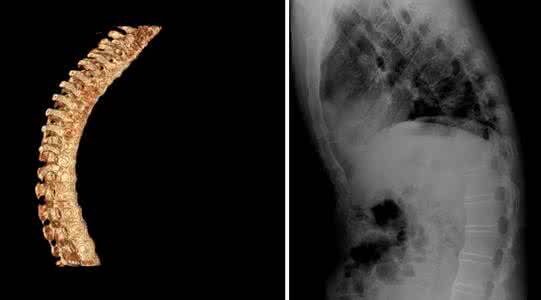

药物只能改进病人腰背部的苦楚和发僵的情况,晚期严峻的变形者则需要做人工全髋关节的置换术来进行治疗。置换术后绝大大都病人的关节痛会得到控治,有些病人的功能胡逐渐康复正常状态或挨近正常。康复训练有助于减轻疾病的表现,防止脊柱的变形。